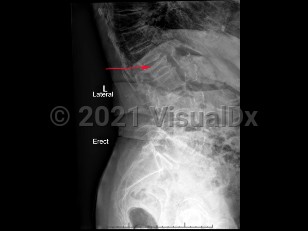

Classic history and presentation: OVCF can present with acute, localized spine pain that infrequently radiates to the ribs. Pain worsens with movement and palpation. However, two-thirds of OVCF are asymptomatic and found incidentally on lateral chest x-ray or with loss of the patient's height.

Grade / classification system: The Genant classification of vertebral fractures is based on morphology of the vertebral body (eg, wedge, biconcave, or crush deformities) and grades the severity of fracture.

- Grade 0 (normal): No vertebral height loss seen

- Grade 1 (mild fracture): 20%-25% vertebral height loss

- Grade 2 (moderate fracture): 25%-40% vertebral height loss

- Grade 3 (severe fracture): > 40% vertebral height loss